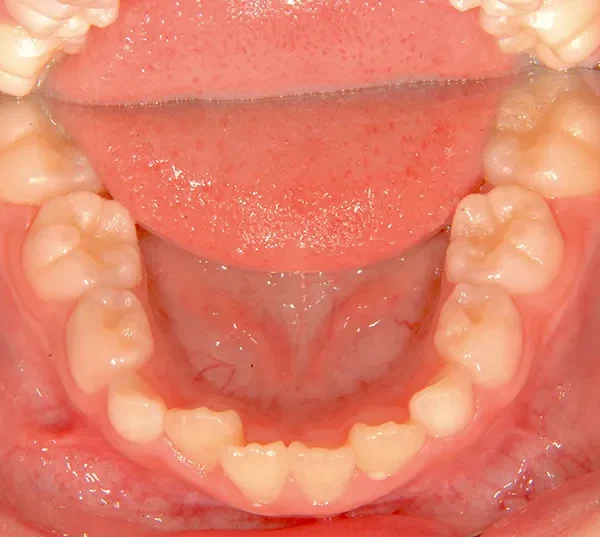

• 治療終了後

治療終了後

まずは装置で歯のアーチを広げ、歯の生えるスペースを作り、中に入ってる上の前歯を外に押し出して正常な噛み合わせにします。

治療回数44回、5年5ヶ月の治療期間で矯正治療を終了しました。

主訴が改善され、ご満足頂きました。